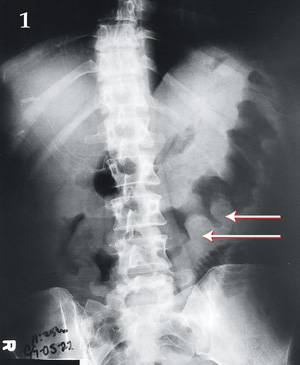

A 39-year-old woman with AIDS (CD4 count, 30 cells/mL) had a 4-day history of nausea, vomiting and profuse watery diarrhoea. The patient was afebrile and had a distended abdomen with diffuse guarding without rebound tenderness. Abdominal x-rays (Box 1) and computed tomography scans (Box 2) were performed. The white blood cell count was within normal limits and stool cultures were negative. Colonoscopy revealed yellow plaques throughout the colon. The patient improved clinically after taking oral metronidazole.

Bowel wall "thumbprinting" (the appearance of "thumbprint"-shaped projections) is a radiological sign of thickening of the colonic wall. It occurs secondary to submucosal haemorrhage and oedema from capillary leakage.1 It can result from any process that leads to oedema of the bowel wall, including pseudomembranous colitis (as shown here), ischaemic colitis, non-infective inflammatory bowel disease, other infective bowel diseases, submucosal/intramural haemorrhage and other conditions.2 The mucosal damage and inflammation seen in pseudomembranous colitis are caused by Clostridium difficile toxin.3